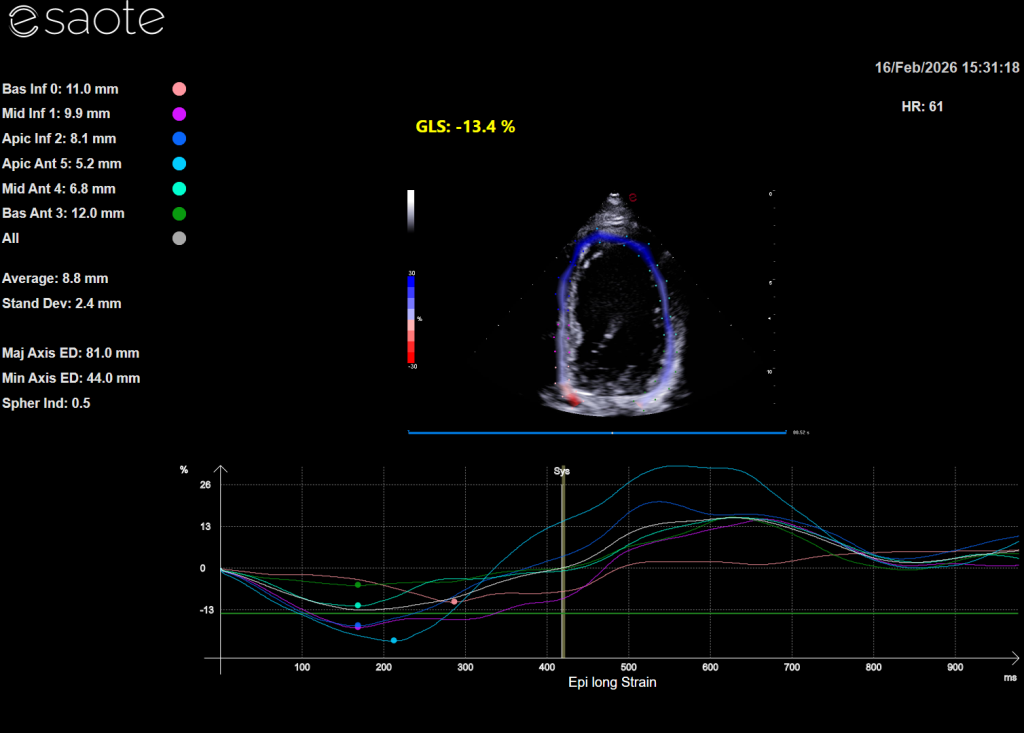

Aby precyzyjnie ocenić ukryte funkcje serca, nowoczesna kardiologia wykorzystuje między innymi wysokiej klasy aparaty ultrasonograficzne. Pozwalają one lekarzowi nie tylko na żywo obserwować pracę zastawek, ale też mapować przepływ krwi i mierzyć grubość ścian mięśnia sercowego z dokładnością do ułamków milimetra – i to wszystko całkowicie bezboleśnie dla zwierzaka.

- Echokardiografię (USG serca): Złoty standard w kardiologii. Pozwala na bezbolesne „zajrzenie” do wnętrza bijącego serca w czasie rzeczywistym, ocenę pracy zastawek i grubości ścian mięśnia sercowego.